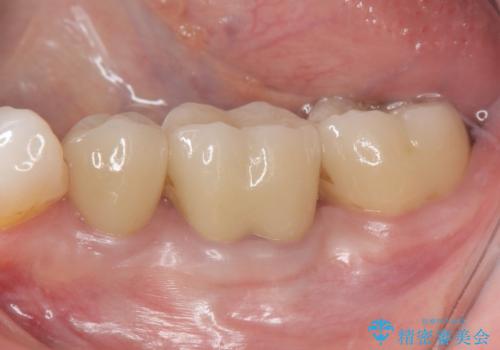

[ジルコニアクラウン] 前歯をきれいに

- 幼少時に行った前歯の治療、経年的に劣化し審美面の改善を求めて来院されました。

長期的な予後を見込むために、根管治療のやり直しから計画します。

- 13万円(仮歯・ファイバーコア・ジルコニアクラウン)費用は治療当時の料金となります

ジルコニアクラウンは色調を合わせることができるため、周囲の歯の色に調和し審美的な仕上がりを期待することができます。